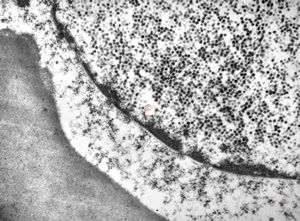

F, 46y. | verruca vulgaris … intranuclear virions

F, 46y. | verruca vulgaris … intranuclear virions

F, 46y. | verruca vulgaris … intranuclear virions

F, 46y. | verruca vulgaris … prominent keratohyalin granules